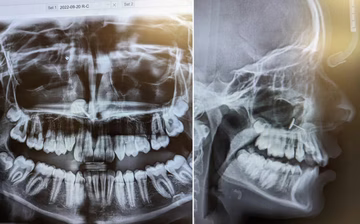

Naredil rentgensko sliko zob: ta je razkrila nekaj, česar nima nihče drug na svetu Magazin | pred 2 min. | 0

Hčer je peljala na rentgen zob. Ta je razkril nekaj, česar ne bi smelo biti tam Magazin | 15. avg | 1